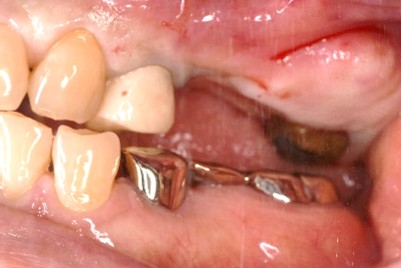

左下、ブリッジの支台になっていた奥のほうを抜歯したままになっている。ここのところを何とかしたい。

治療内容

ブリッジの奥に伸びていた部分を削り取り、インプラントを2本入れました。

所感

左下ブリッジのところを切り離し、奥を抜歯したままになっていました。このままでは、ブリッジの前方の支台になっていた歯に負担がかかり、将来抜歯になる可能性があることをお話ししました。歯がないところを補う方法には、部分入れ歯かインプラントがあることを説明すると、自分の歯と同じ感覚で食事ができるインプラントを選択されました。X-Guideを使用し埋入しました。口を大きく開けることができない方でしたので、X-Guideの長所のうちの一つを活かすことができました。

インプラント2本:¥363,000×2本=¥726,000(税込)

Before

青丸の部分を削り取りました

After